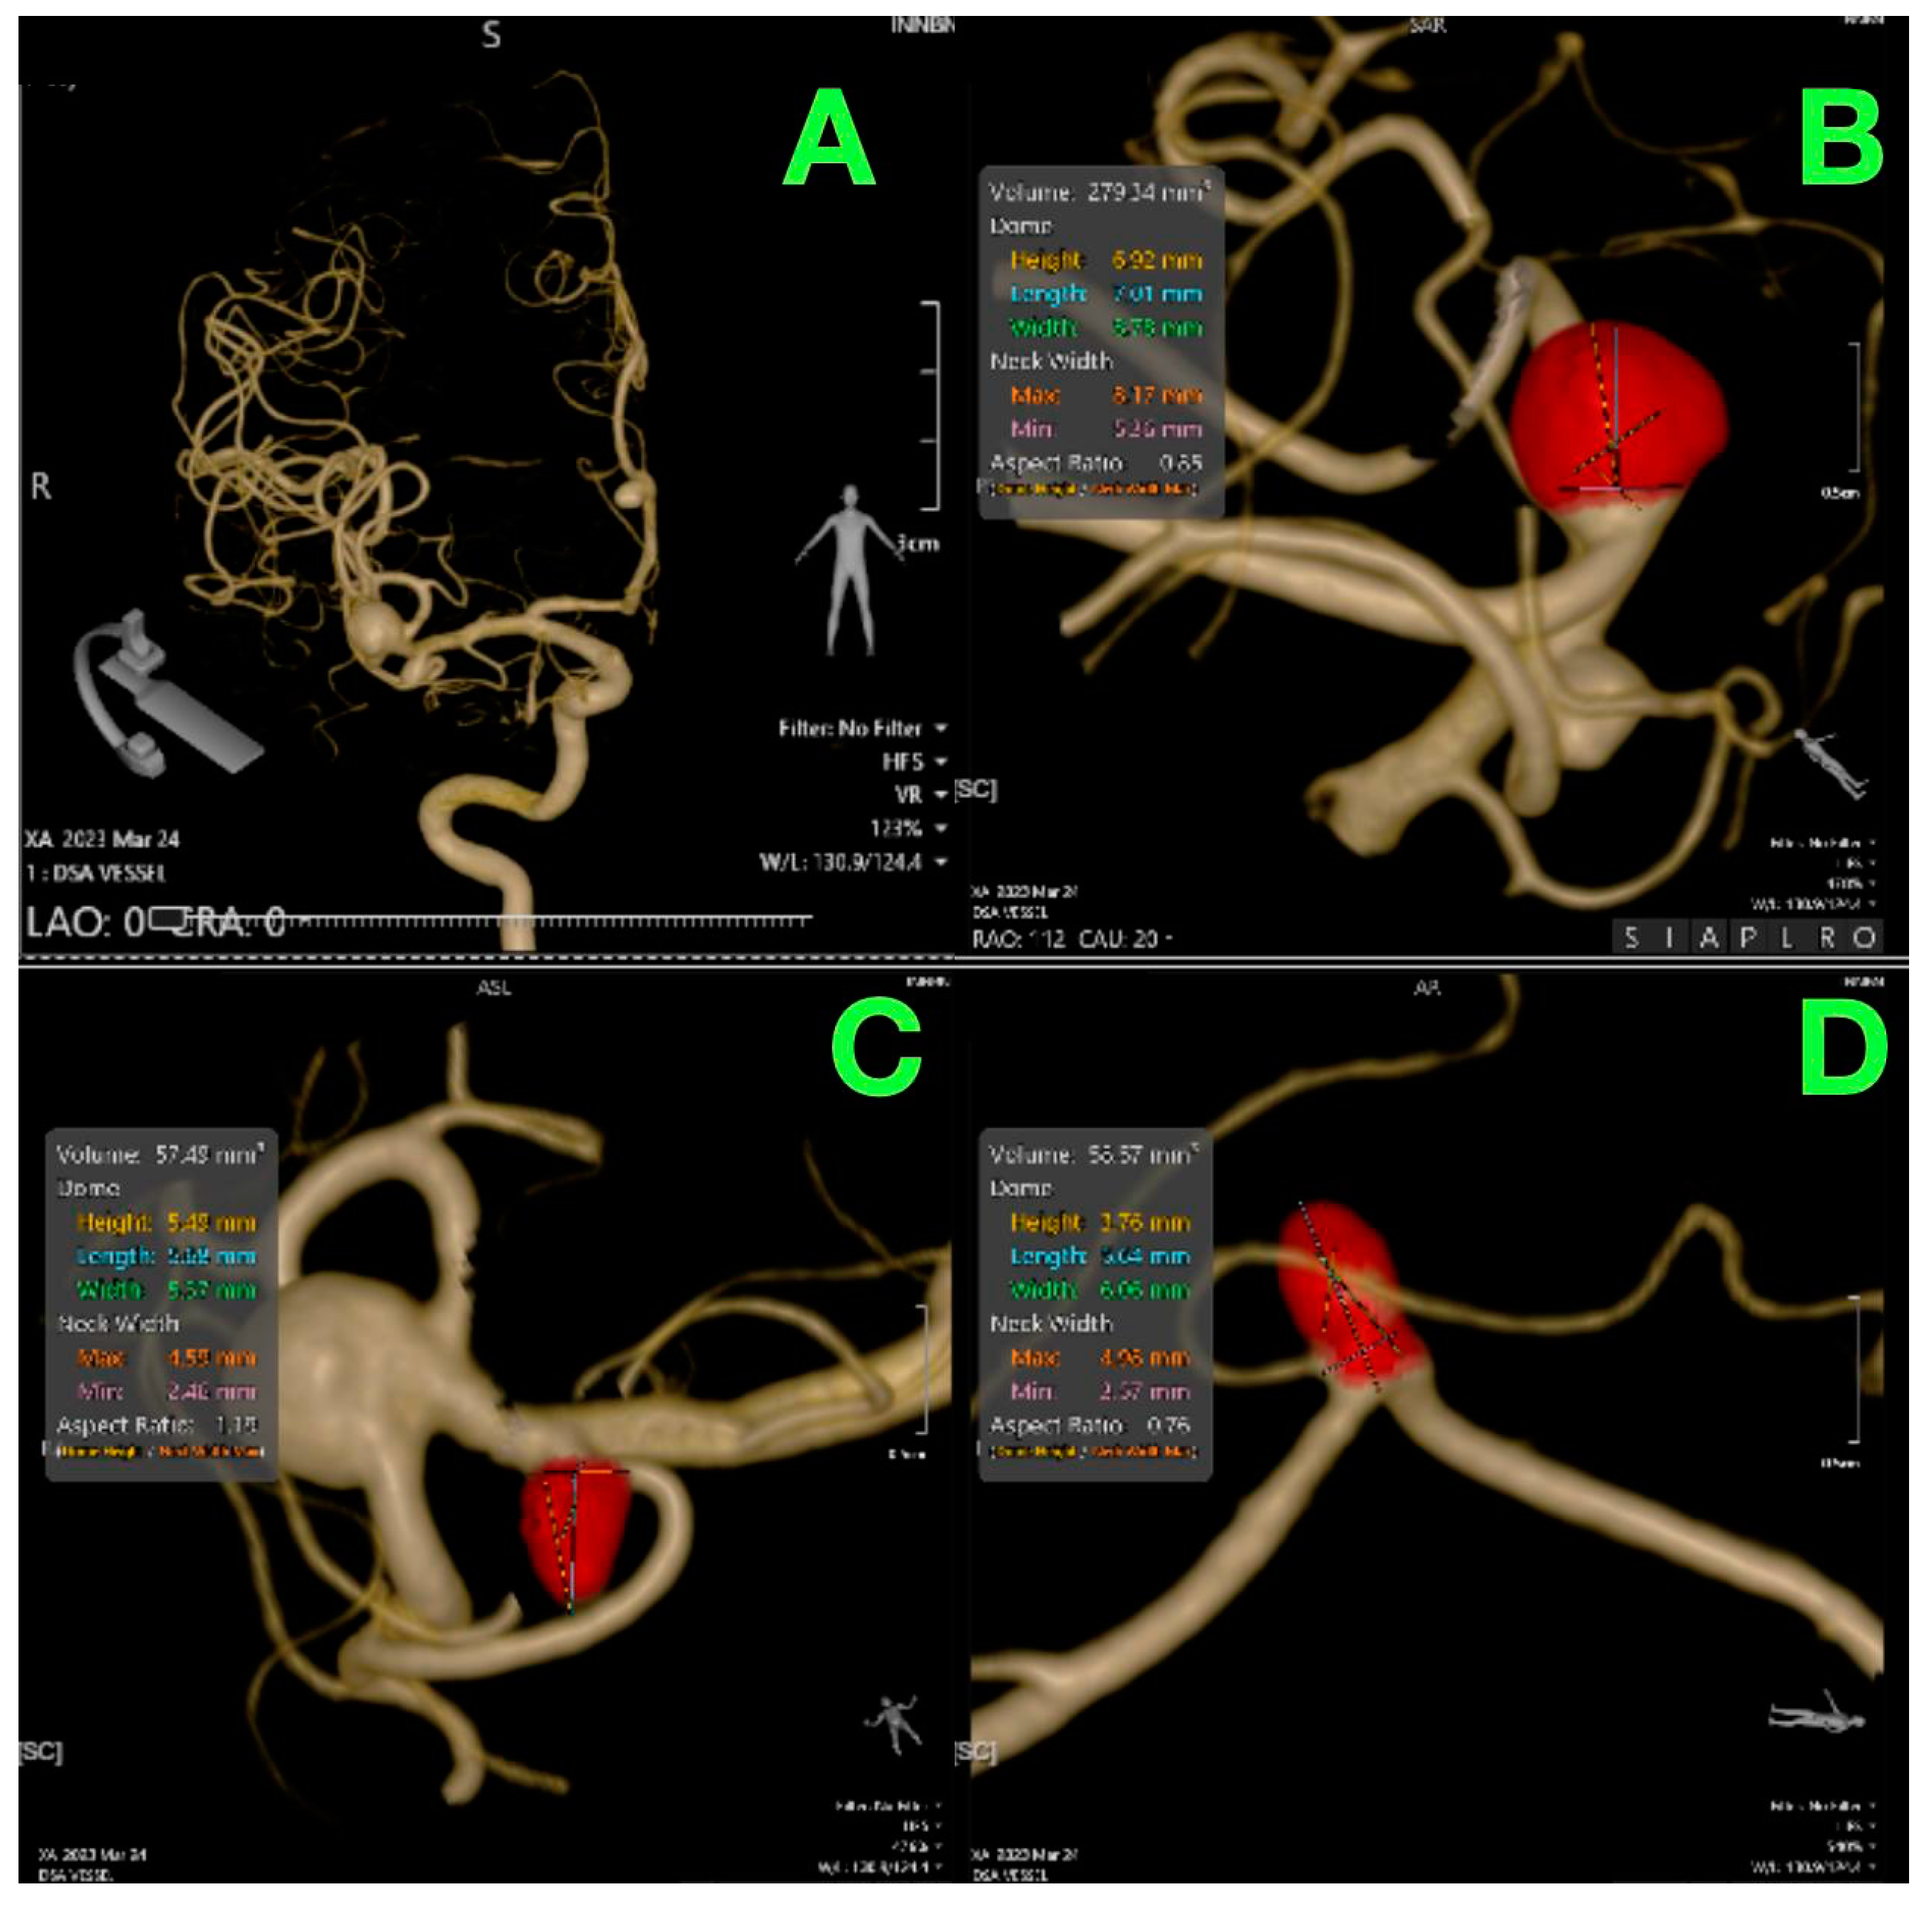

2. Case Presentation